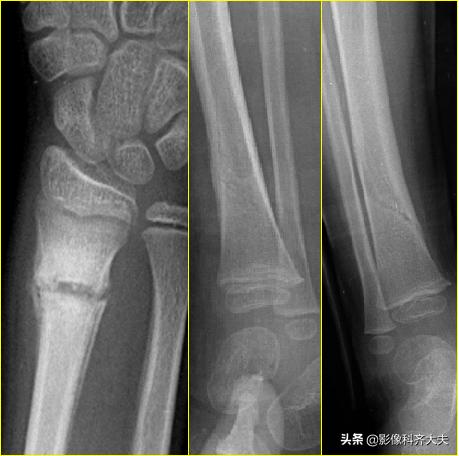

胫腓骨远端骨折

Colles骨折:伸展型桡骨远端骨折,在桡骨远端2-3cm以内的横行或粉碎骨折,远侧向桡或背侧移位,常合并尺骨茎突骨折。